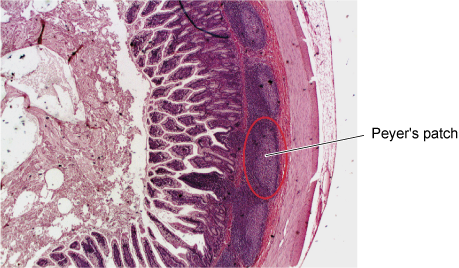

There are large numbers of lymph nodes in the abdomen surrounding the GI tract. In addition, the majority of immune cells in the body are located in specialised areas of gut-associated lymphatic tissue (GALT) mainly located in the wall of the small intestine (Figure 16). The tonsils, adenoids and appendix are all GALT.